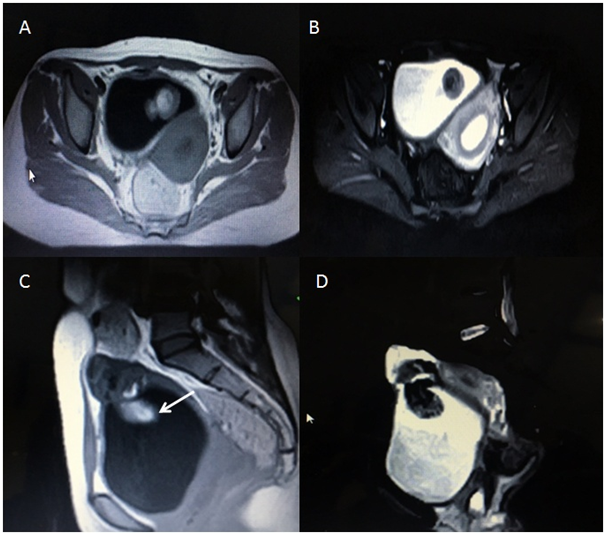

There was a pelvic ultrasound done by a local sonologist which reported a mass in the urinary bladder with normally visualized both ovaries & uterus. The scan was repeated and revealed an intra vesicular echogenic mass (Figure 2) with normal right ovary and uterus. However; left ovary was not visualized. Due to non visualization of the Ovary, the patient was advised to get a pelvic MRI, which revealed a mixed intensity lobulated well defined mass along the dome of the Urinary bladder with both intra & supra vesicular components (Figure 3). There were internal T1 hyper intense areas showing low intensity on fat suppression and a focus of signal void; suggesting internal fat and calcific intensities, respectively. Few small cyst like foci (follicles) could be visualized in the supra vesicular component of the mass with non visualized separate left ovary. Right ovary and Uterus were normal. Diagnosis of Left Ovarian dermoid cyst with cysto-vesical fistula was made. In view of academic interest and for diagnostic correlation, pelvic CT scan was acquired; under complete patient satisfaction and informed consent (Figure 4).

Figure 3 Pelvic MRI showing a well defined supra and intra vesical mass with breech in the dome of the bladder. (A) Axial T1 W image & (C) Sagittal T1 W image showing intra luminal bright area (shown by white arrow) with corresponding suppression on STIR (B & D) images s/o fat intensity.